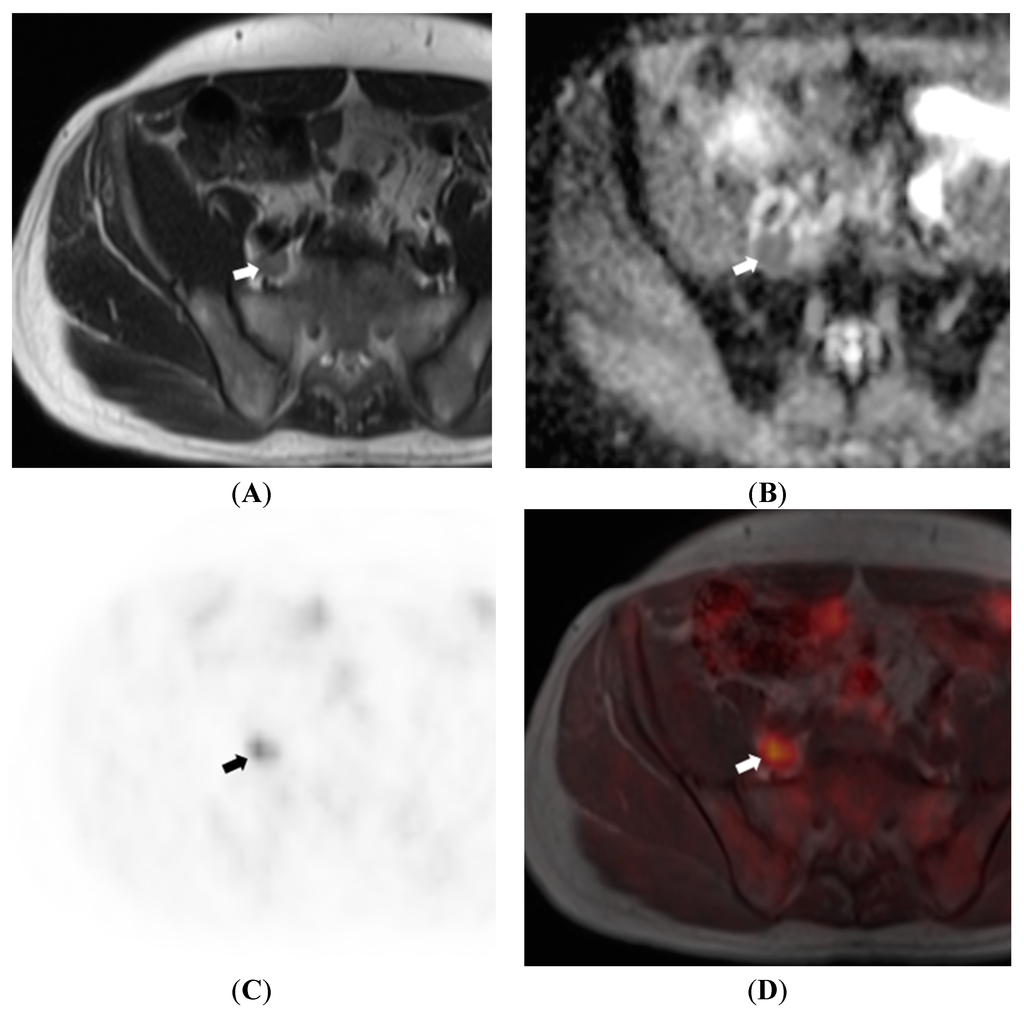

6. Nodal Assessment

- Kim, S.-K.; Choi, H.J.; Park, S.-Y.; Lee, H.-Y.; Seo, S.-S.; Yoo, C.W.; Jung, D.C.; Kang, S.; Cho, K.-S. Additional value of MR/PET fusion compared with PET/CT in the detection of lymph node metastases in cervical cancer patients. Eur. J. Cancer 2009, 45, 2103–2109. [Google Scholar] [CrossRef] [PubMed]